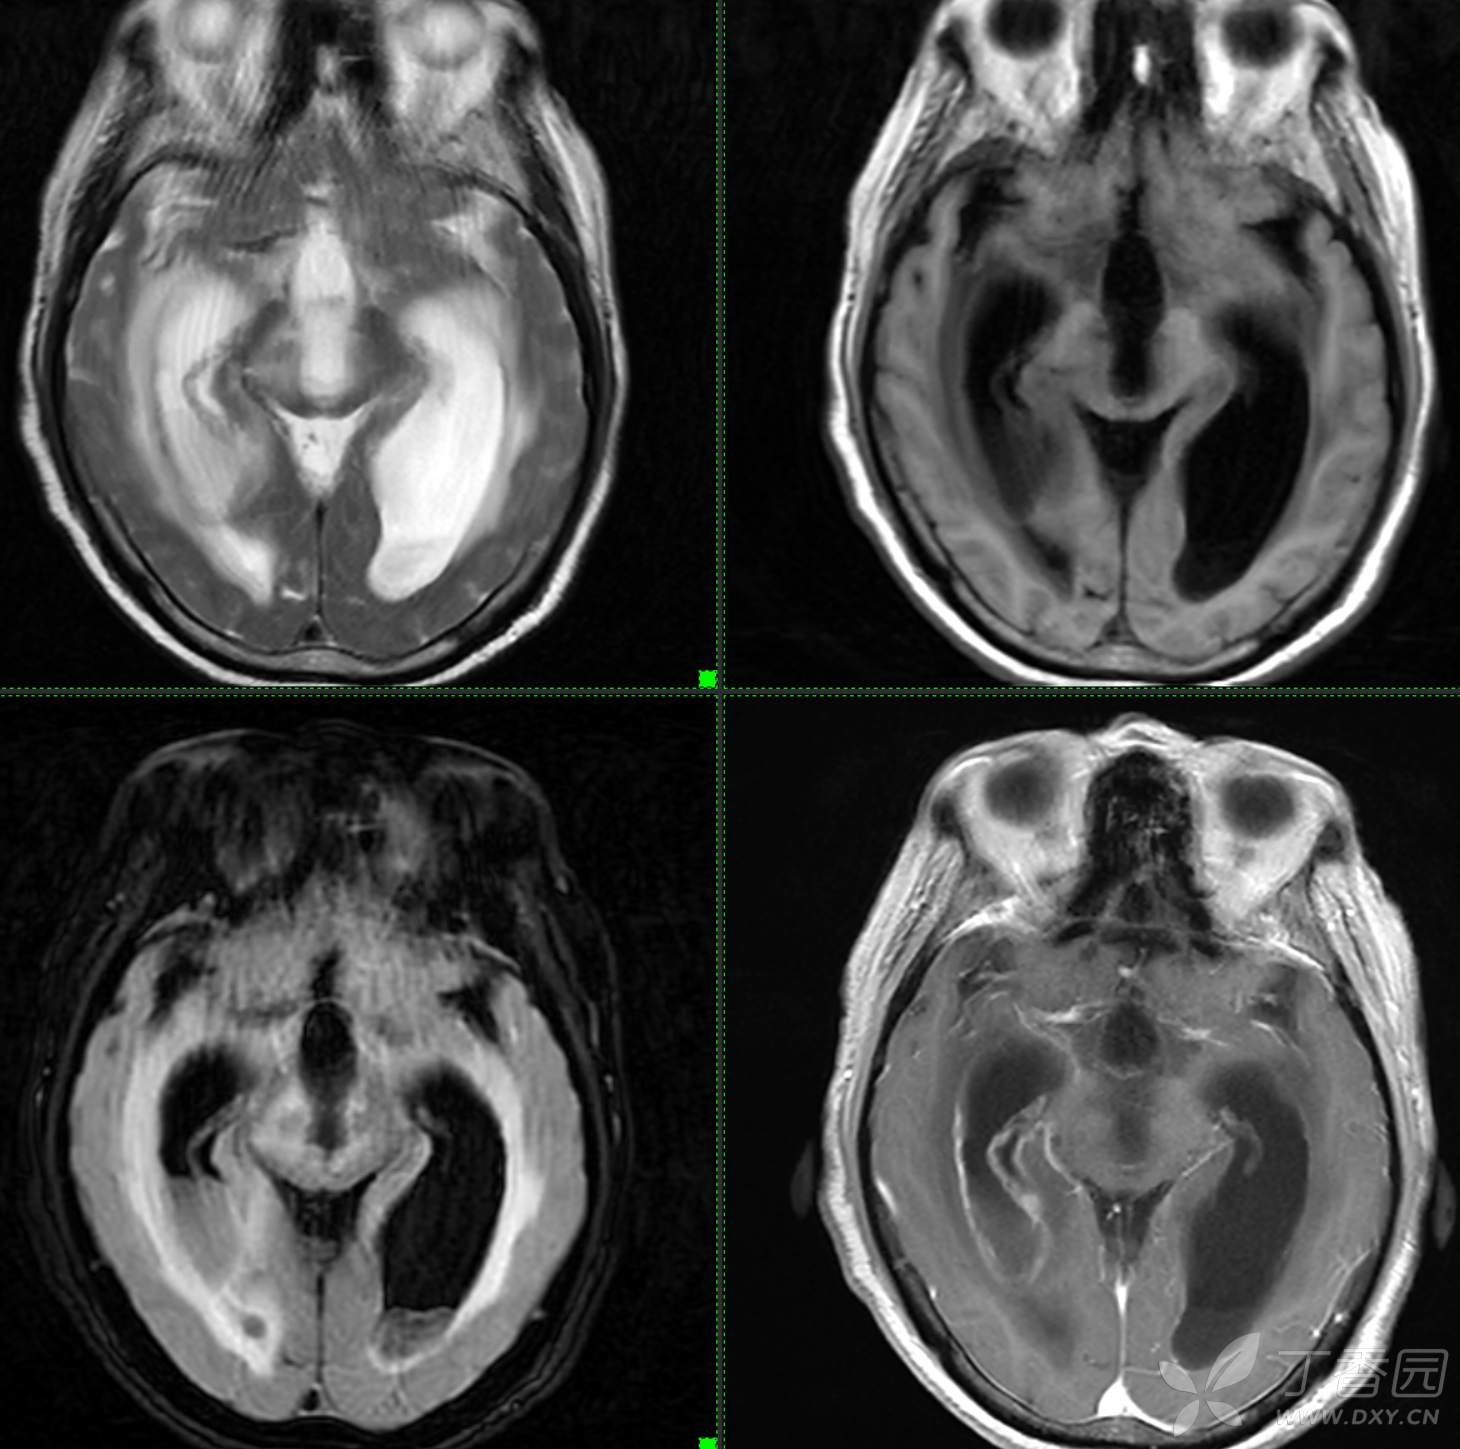

头颈组9:简单分析,诊断不难。

主诉: 【头晕乏力数周,发热1周】

现病史: 患者3周前无明显诱因下出现头晕,无头痛,伴视物模糊,肢体乏力,走路步态不 稳,无意识不清,对答切题,当地医院查血常规示:中性粒细胞分类:77.7%.淋巴细胞分类:15.6%,中性性粒细胞分类:7.1*10^9/L.葡萄糖:22.35mmol/,头颅平扫示:右侧丘脑饱满,密度减低伴低密度灶,占位不排除,两侧半卵圆区、额叶低密度灶,以“1.糖尿病酮症酸中毒,2.颅内占位性病变”收入住院治疗,1周前住院期间出现发热,先后予抗感染,控制血糖等对症支持治疗,2天前无明显诱因下再次出现发热,伴血糖升高,自测体温40℃,血糖20mmol儿,伴气促无胸闷,袖志模糊,反应迟钝,无畏寒寒战,无腹痛腹泻等不适,昨日送至我院就诊